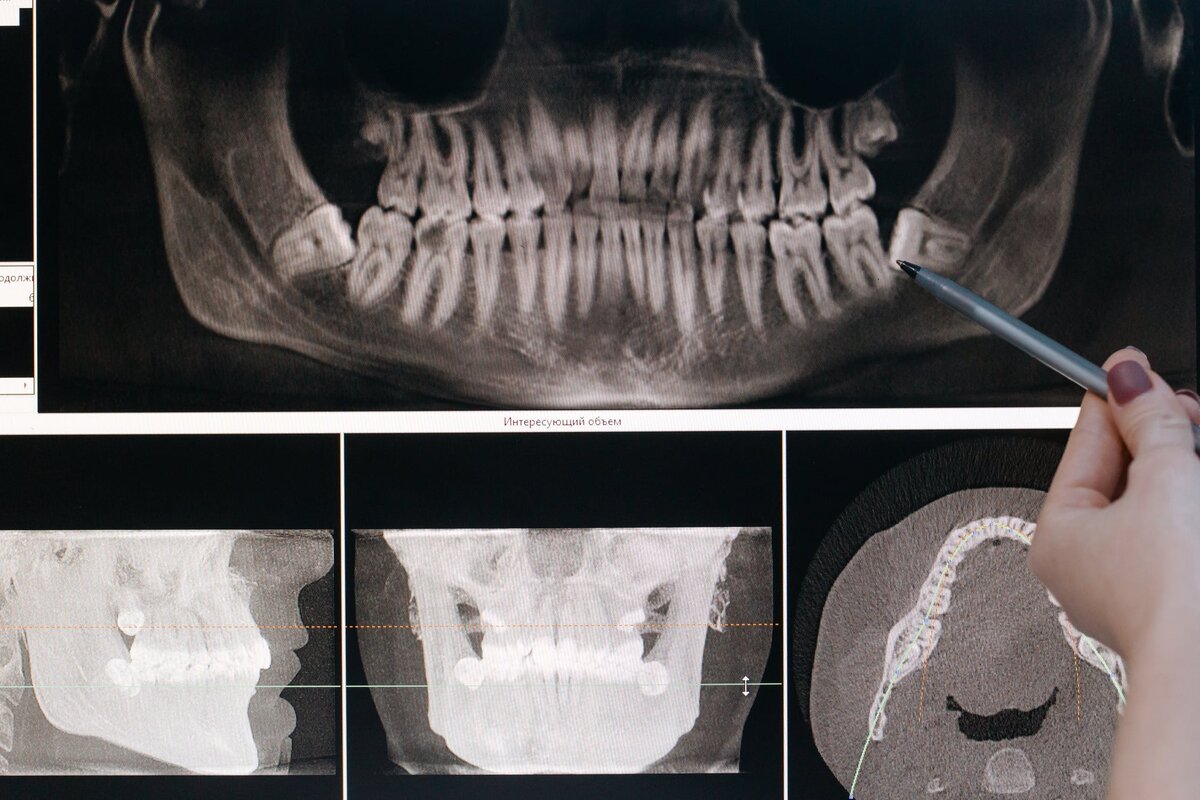

Снимок зубов

🔹Остатки в лунке

Иногда после удаления зуба в лунке остаются мелкие зубные осколки. Осложнение сопровождается воспалительным процессом, повышением температуры. Если отсутствуют признаки заживления тканей и появились симптомы воспаления, необходимо пройти рентгенографию. На снимке будут видны возможные остатки зуба в лунке.